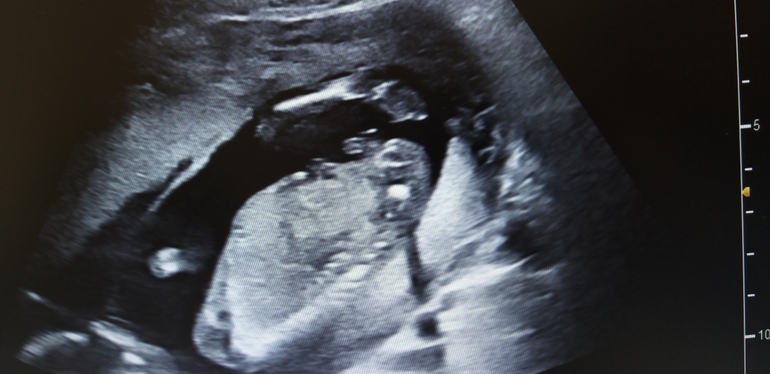

УЗИ в 16 недель(фото с экрана, голова внизу попка и перчик наверху)